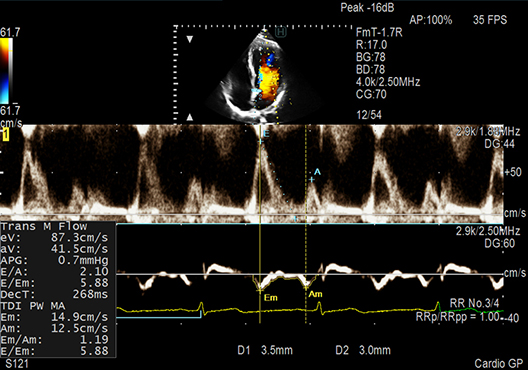

E/e', one of the key LV diastolic performance indices, is measured automatically in Dual Gate Doppler use. By using this in combination with R-R Navigation, iDGD detects an appropriate heartbeat for measurement.

- Dual Gate Doppler: Enables observation of Doppler waveforms from two different locations in the same heart cycle.

- R-R Navigation: Enables the detection of a stable R-R interval automatically.